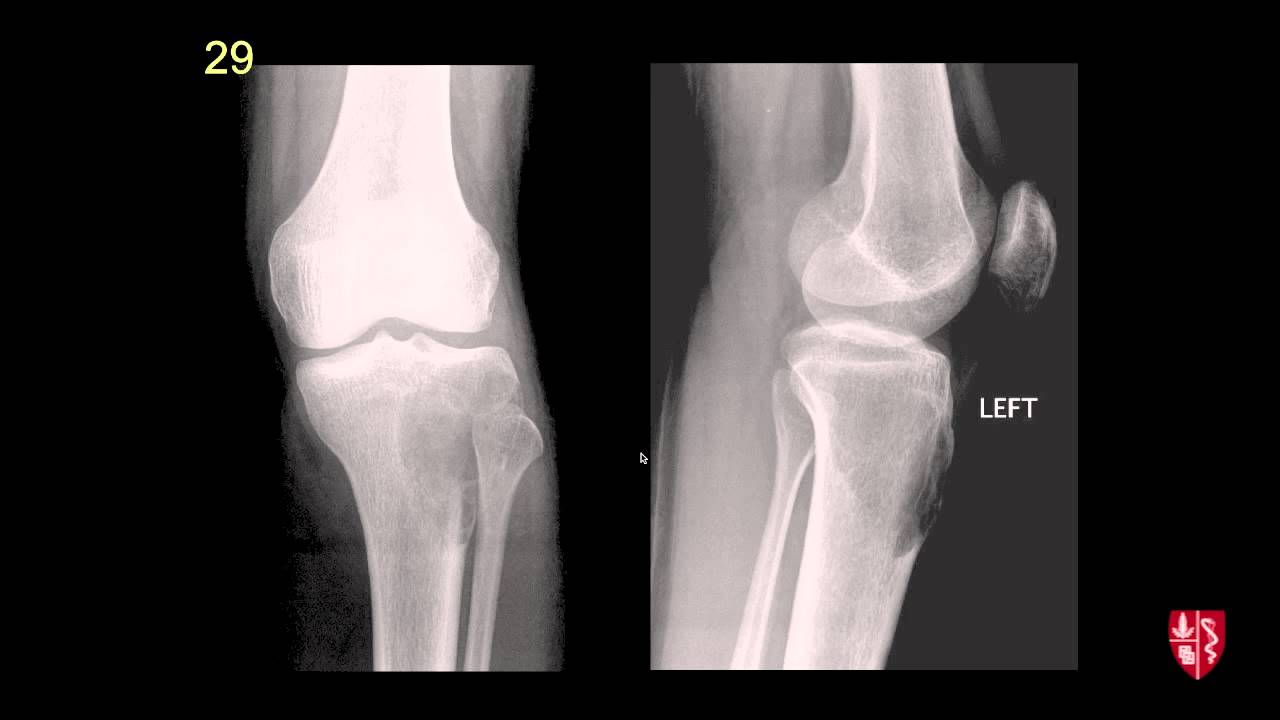

Essential radiography of the upper extremity

Basic radiographic imaging of the upper limb from Stanford.